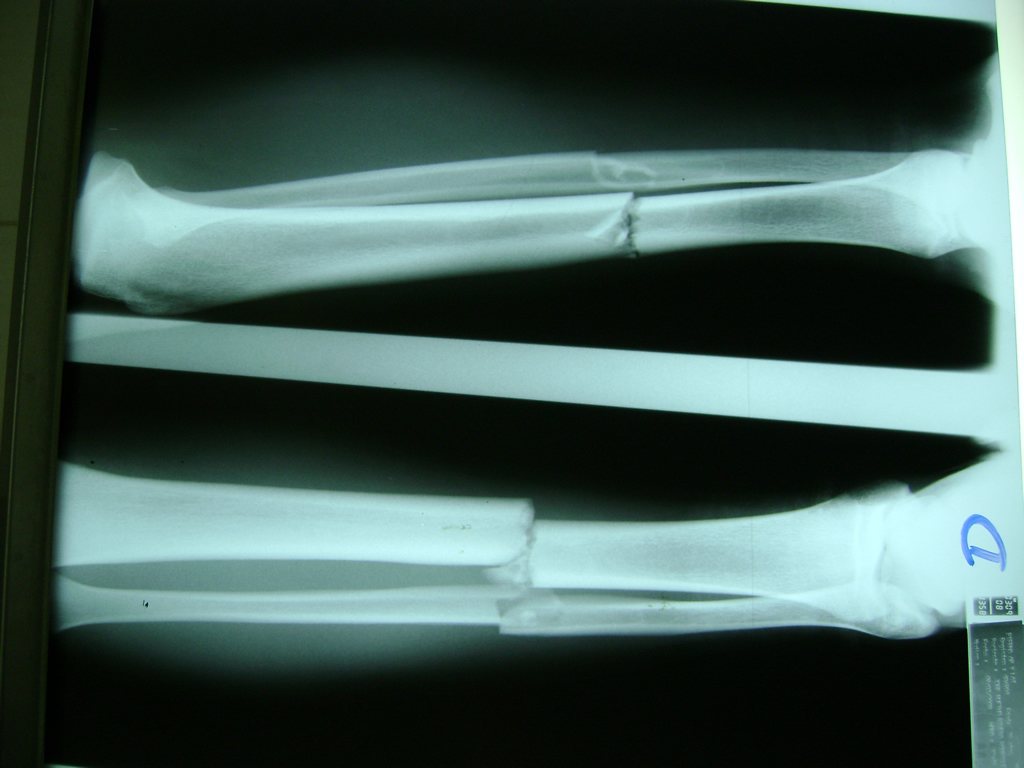

Calcaneo - Perone y Tibia

Aunque cada uno de estos huesos puede fracturarse por separado, normalmente la rotura es una lesión que se produce de forma conjunta

La mayor parte de las roturas implican a la parte proximal del hueso (parte del hueso próximo a la rodilla) o a la parte distal (parte del hueso cerca del tobillo).

Debido a la fina cobertura de piel que recubre la tibia y el peroné, las fracturas generalmente son abiertas, es decir, el hueso roto rasga la piel, atravesándola. Las fracturas de tibia y peroné generalmente se producen por un fuerte impacto o torsión.